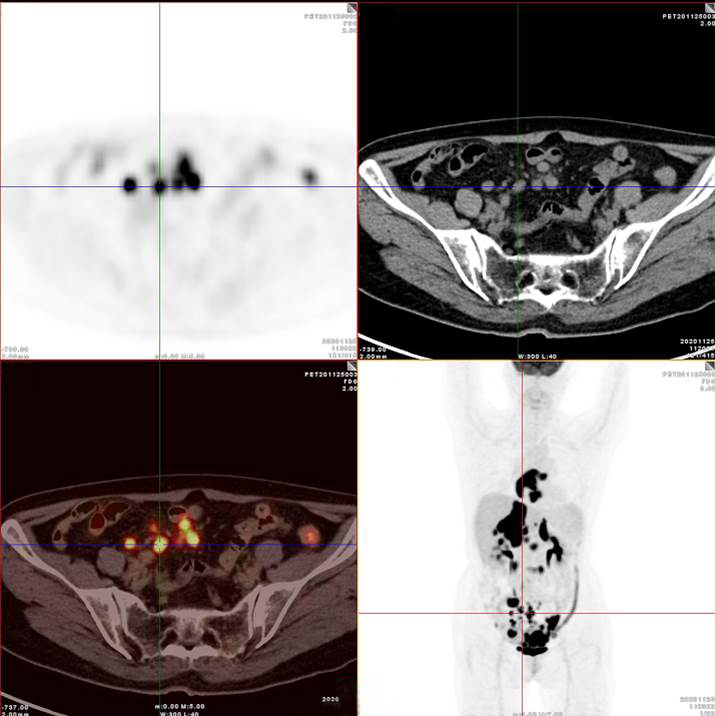

PET/CT影像圖

雙側(cè)腎上腺病灶、腹膜后淋巴結(jié)放射性攝取明顯增高

膽囊及雙腎上腺病灶、腹膜后淋巴結(jié)放射性攝取明顯增高

胃、雙腎上腺病灶、腹膜后淋巴結(jié)放射性攝取明顯增高

腸系膜多發(fā)淋巴結(jié)放射性攝取增高

多段小腸腸管放射性攝取增高